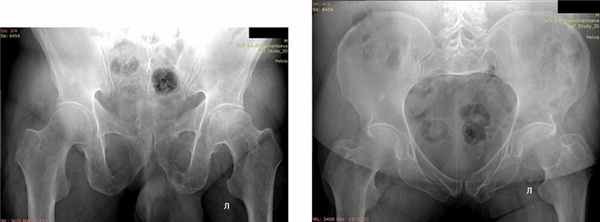

Клинический пример 1. Пациентка Р., 68 лет, травма в результате ДТП, пассажир. Доставлена бригадой скорой медицинской помощи (СМП). Установлен диагноз: политравма. Перелом боковых масс крестца справа Denis I. Перелом седалищной кости справа со смещением отломков. АО/ОТА — 61-В2.1 Перелом поперечных отростков слева L3–L5 (рис. 1). Рис. 1. Пациентка Р., 68 лет. Компьютерная томограмма, 3D-реконструкция, визуализирован перелом поперечных отростков слева L3–L5. Перелом боковых масс крестца слева Denis I. Закрытый перелом дистального метаэпифиза обеих костей правого предплечья со смещением отломков. Ушиб грудной клетки. По шкале ISS 21 балл.

Отдаленные результаты через 12 мес: на контрольных рентгенограммах определялись консолидированные переломы боковых масс крестца справа, седалищной кости справа (рис. 2). Рис. 2. Пациентка, Р. 68 лет. Рентгенография консолидированного перелома боковой массы крестца справа через 12 мес после операции. Остеосинтез канюлированным винтом. Консолидированный перелом седалищной кости справа. а — проекция: выход из таза; б — проекция: вход в таз. По шкале S. Majeed — 85 баллов, по тесту «Timed up & go» [30] 9 с (рис. 3). Рис. 3. Пациентка Р., 68 лет. а–в — внешний вид и функция через 12 мес после операции.